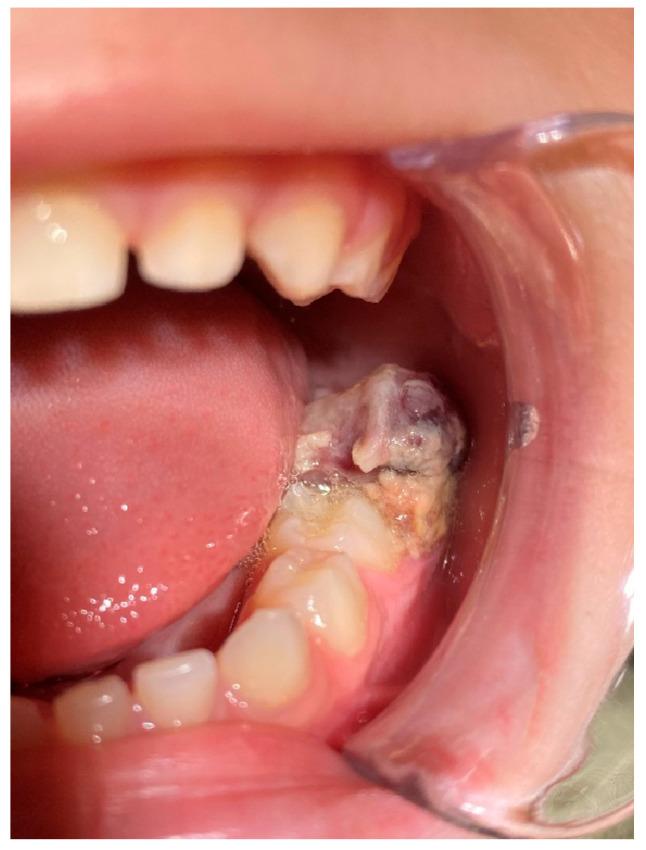

一名6岁男性患者被转诊至希腊塞萨洛尼基亚里士多德大学健康科学学院牙科学院口腔医学/病理学系的研究生诊所,因为他的儿科牙医在常规检查中发现牙齿#75远中处有一个外生性口腔内肿块。首次组织病理学检查显示为牙龈肿瘤,归类为小圆蓝细胞瘤,与釉质瘤样尤因肉瘤(ALES)更为相似,与滑膜肉瘤的相似性较小。第二位病理学家检查了相同的组织标本,并提示极罕见地存在未成熟恶性畸胎瘤。化疗后,切除了畸胎瘤剩余部分及相邻的牙齿#75,组织病理学检查显示为成熟畸胎瘤。